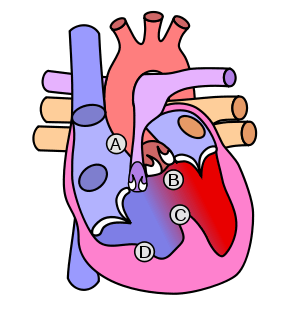

Blood flow diagram of the human heart. Blue components indicate de-oxygenated blood pathways and red components indicate oxygenated blood pathways. | |

The heart

As the center focus of cardiology, the heart has numerous anatomical features (e.g., atria, ventricles, heart valves) and numerous physiological features (e.g., systole, heart sounds, afterload) that have been encyclopedically documented for many centuries.

The primary responsibility of the heart is to pump blood throughout the body. It pumps blood from the body — called the systemic circulation — through the lungs — called the pulmonary circulation — and then back out to the body. This means that the heart is connected to and affects the entirety of the body. Simplified, the heart is a circuit of the Circulation. While plenty is known about the healthy heart, the bulk of study in cardiology is in disorders of the heart and restoration, and where possible, of function.

The heart is a muscle that squeezes blood and functions like a pump. Each part of the heart is susceptible to failure or dysfunction and the heart can be divided into the mechanical and the electrical parts.